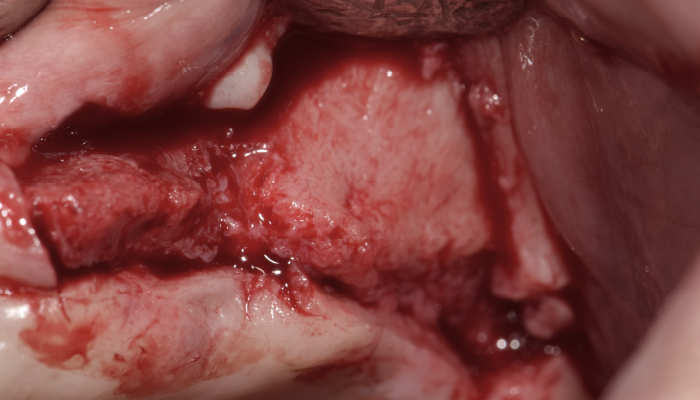

매복 사랑니 발치

이OO님 전후사진 / 치료 기간 : 30분 / 당일 사랑니 발치

매복 사랑니 발치

심OO님 전후사진 / 치료 기간 : 30분 / 당일 사랑니 발치

매복 사랑니 발치

서OO님 전후사진 / 치료 기간 : 30분 / 당일 사랑니 발치

매복 사랑니 발치

김OO님 전후사진 / 치료 기간 : 30분 / 당일 사랑니 발치

당일 사랑니 발치

이OO님 전후사진 / 치료 기간 : 30분 / 당일 사랑니 발치

매복 사랑니 발치

노OO님 전후사진 / 치료 기간 : 30분 / 당일 사랑니 발치